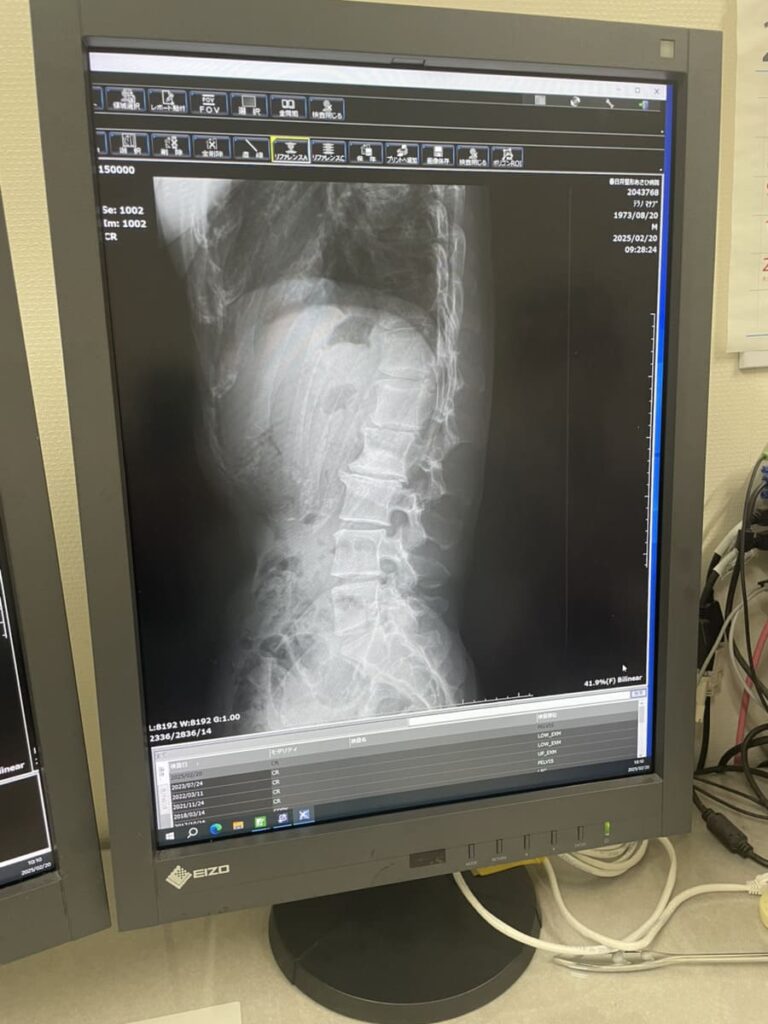

レントゲン写真では、変形のある腰椎以外にも椎間が狭くなっている所がありますし、S字カーブが崩れているように見受けられます。

側湾に関しては神経学としての

以前、作業療法士の方に教えてもらったのですが側湾は呼吸の確保を優先していくと良いとの話でした。(側湾の状態によって異なるとは思いますが)

側湾によって肺の動きに制限がかかって呼吸が浅くなっていないか?

動きの悪いと感じる肺の側を広げて(側屈)深い呼吸をしてまずは肋骨を前後左右に広げられる様に練習することも大切だと思います。